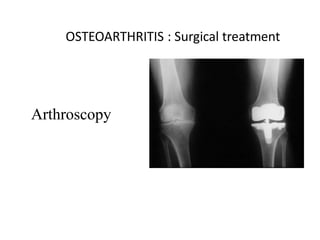

OSTEOARTHRITIS : Surgical treatment

Arthroscopy Osteotomy

Arthrodesis Excision

arthroplasty

Replacement arthroplasty

OSTEOARTHRITIS : Surgicaltreatment Arthroscopy Osteotomy Arthrodesis Excision arthroplasty Replacement arthroplasty